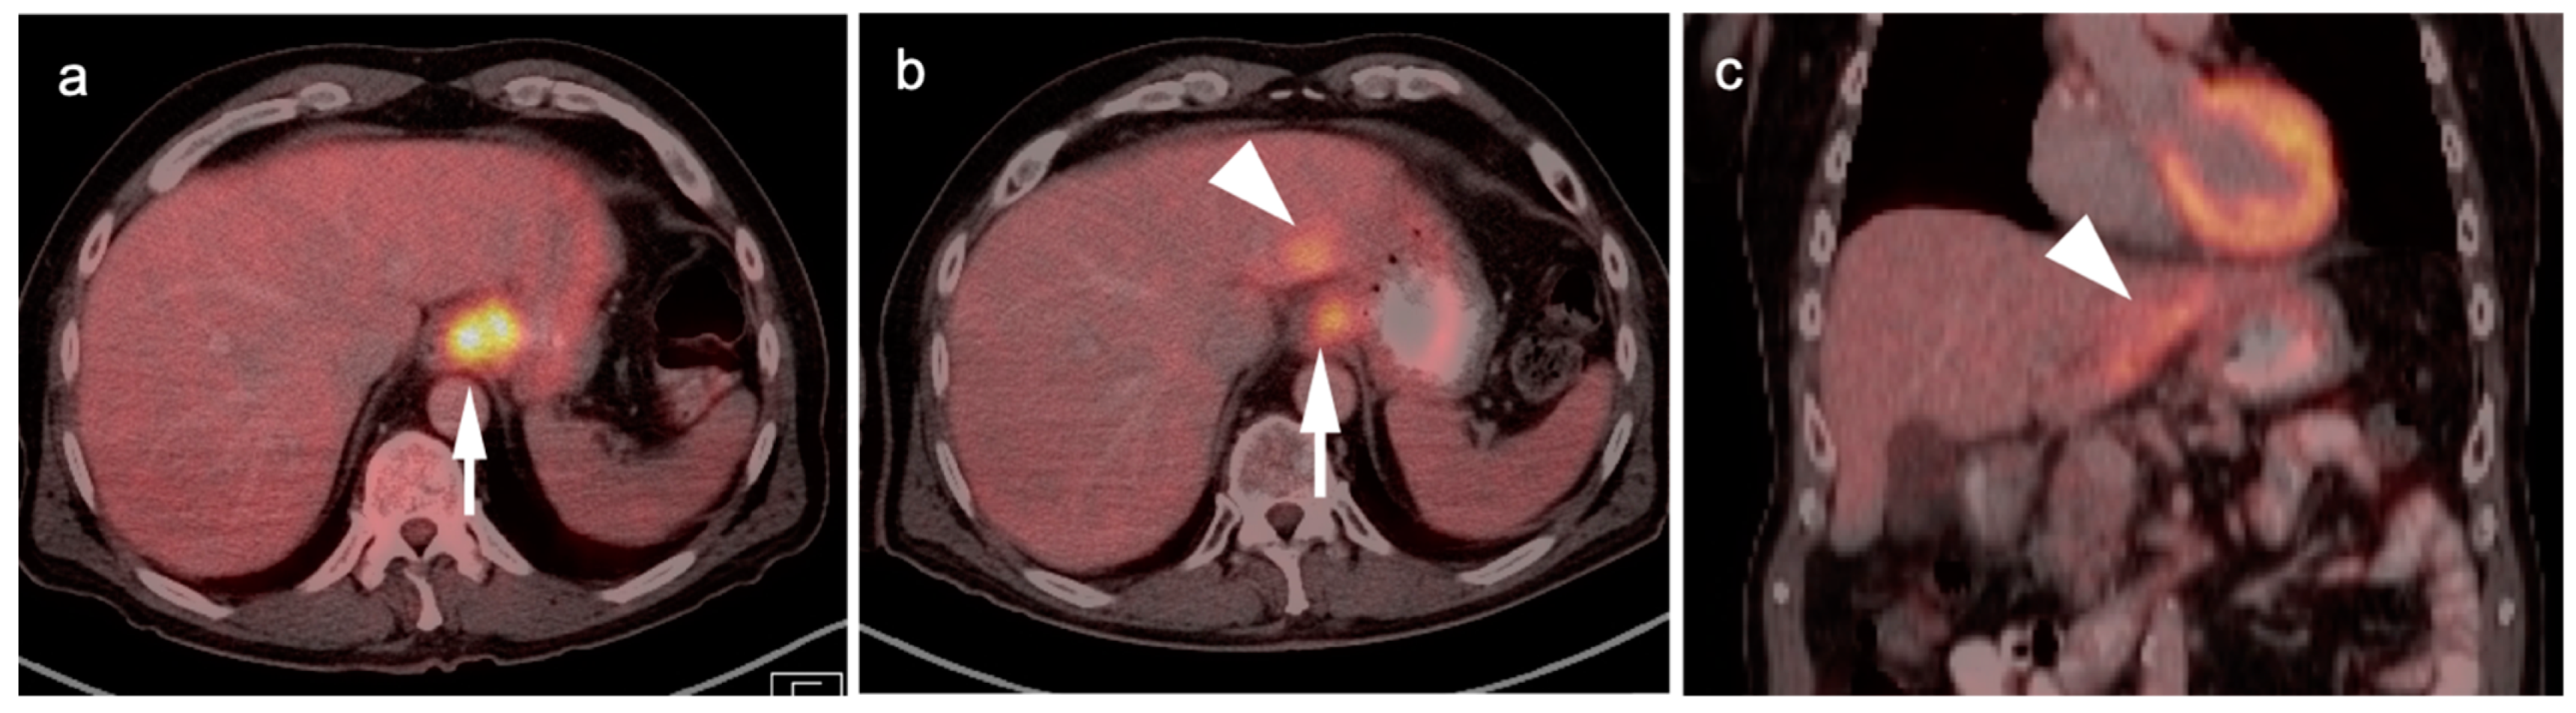

5. Cholangiocarcinoma